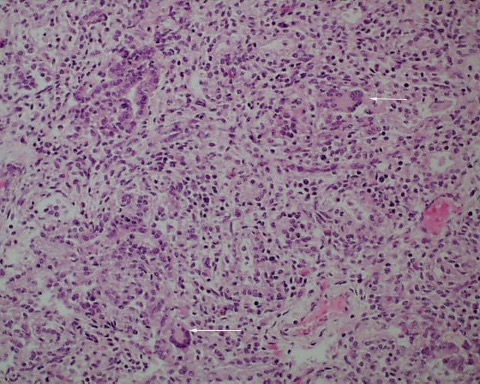

Infection: Even without gasping, microorganisms and neutrophils present in infected amniotic fluid would be able to traverse into the airways from normal, shallow respiration. This is also likely true for mobile neutrophils in the amniotic fluid. In previable fetuses, cuboidal cells lining the airways shed into the lumen and undergo karyorrhexis (apoptosis) that may resemble, but are morphologically distinct from neutrophils (fig 11a,b).

However, the karyorhectic cells lack the intact cytoplasm of neutrophils. It is not possible to observationally determine whether neutrophils in the airway are from aspiration of neutrophils in the amniotic fluid, or are from fetal neutrophils in response to aspirated bacteria. The exception is with focal bronchopneumonia which demonstrates a fetal inflammatory response with large, focal accumulations of neutrophils and vasodilatation of surrounding capillaries (fig 12a,b).